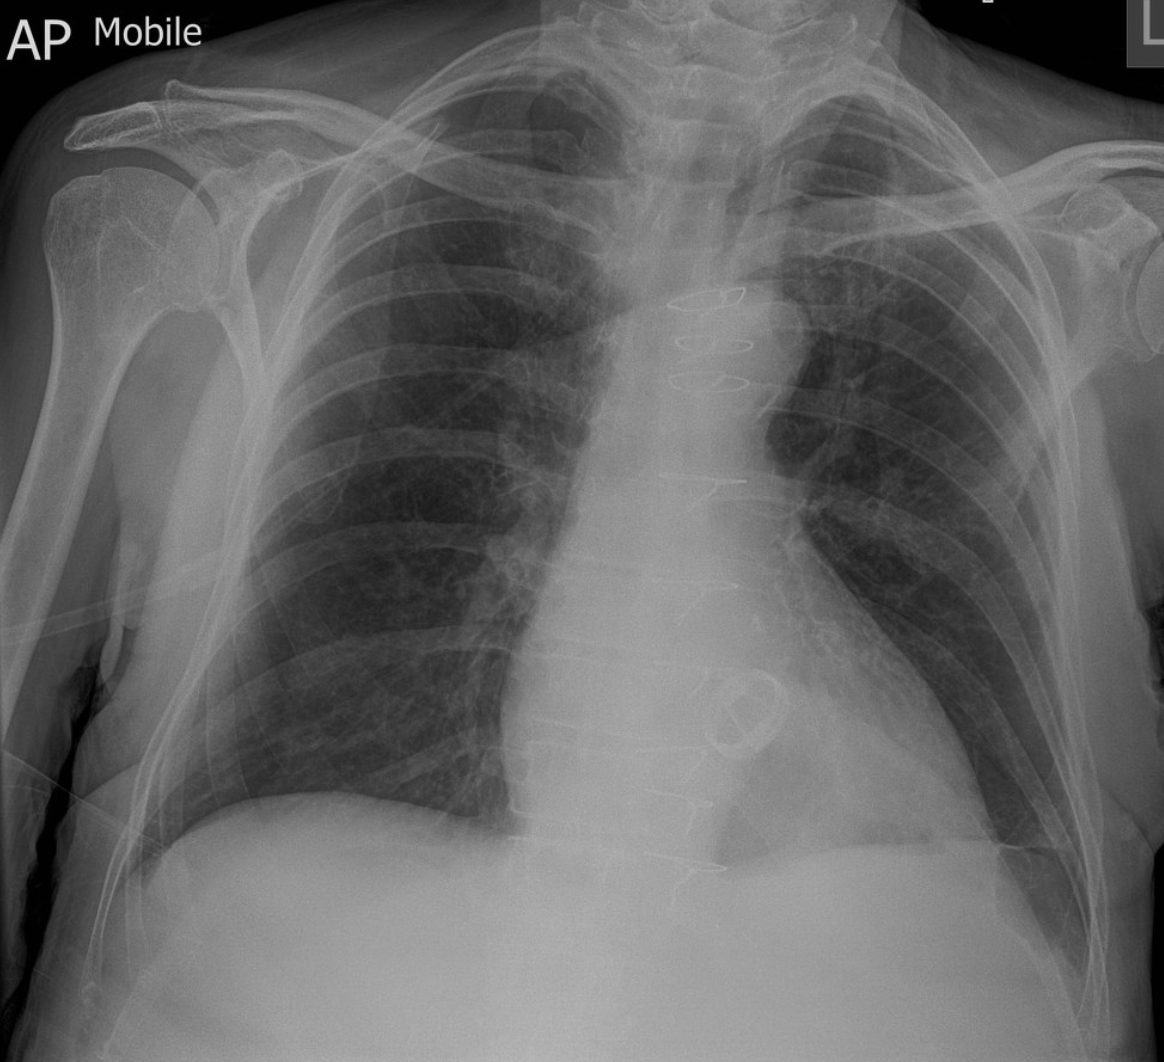

32

-Dual chamber pacemaker -Left sided Pneuomothorax